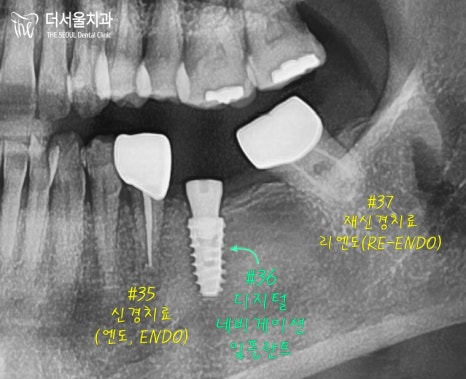

브릿지 를 뜯어내고 내면을 확인해 보니

머리 부분이 다 썩어이서

35번은 신경치료 와

37번은 리엔도(re-endo) 가 필요했었죠.

35번과 37번을 각각 씌우고

가운데 비어있는 36번은

디지털 임플란트 를 심어 드렸습니다.